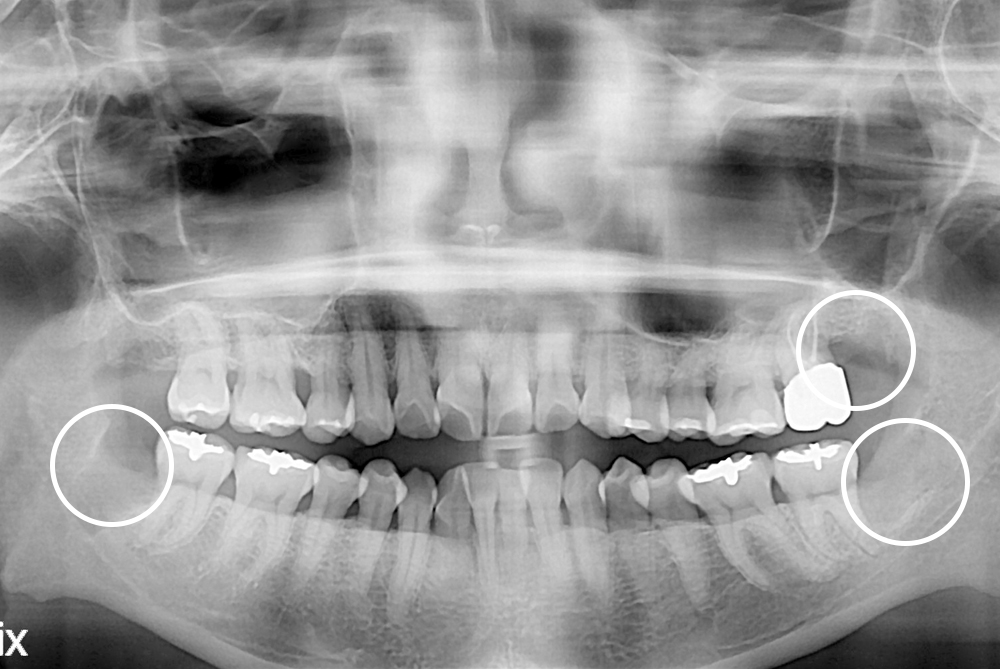

[사랑니] 매복 사랑니 발치

치료후 : 2018-12-03

세종치과는 구강악안면외과학 박사이신 원장님이 발치하는 치과입니다.